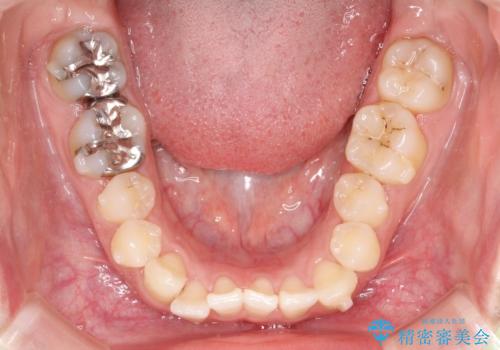

初診時の歯並びの状態としては、上下ともに前歯部の中等度のがたつきがあり、特に左上の前歯が1本内側に入り込んでしまっている状態でした。

また、2mm程度の正中離開がありました。